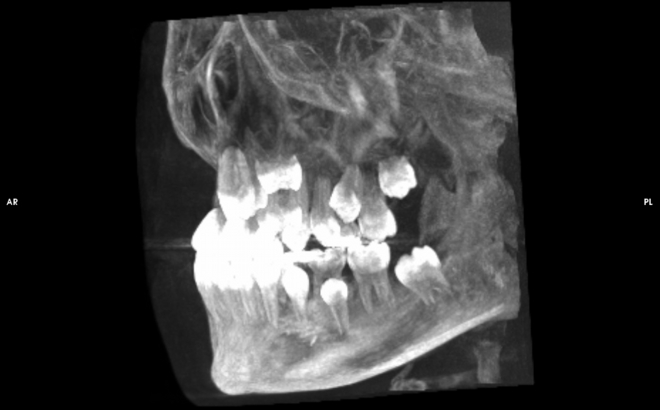

歯や骨を3次元で分析するCT、被爆線量の小さいデジタルパノラマ

レンゲン機器には被爆線量の小さいデジタルパラマ写真(歯列全体歯のレントゲン写真)、歯科用コーンビームCT(顔や顎の変形、埋伏歯や歯根の破折、インプラント治療時の骨や血管・神経の状態などがわかります)、頭部X線規格写真(上顎骨と下顎骨の位置や大きさがわかります)、デンタルX線写真装置があります。